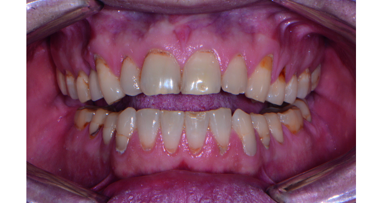

A periodontist and ITI colleague whose office is two hours from our practices referred this patient to our team. Initially, she was seen by the prosthodontist, Dr Harry Randel, and subsequently referred to the periodontist, Dr Robert Levine, for a team approach to solve her failing dentition. The patient presented at our office as a 65-year-old non-smoking female (ASA 3: Illnesses under treatment: anxiety/ depression, osteoarthritis, fibromyalgia, hypothyroidism and history of myofacial pain dysfunction, Figs. 1–3). There was a history of TMJ issues (i.e. clicking and pain with her right side TM joint) which presently is under control and pain-free.

Her chief complaint was to improve her aesthetics and comfort with a desire for a permanent and quick solution to replace her failing dentition. She also desires a reduction of her maxillary anterior gummy smile in the final prosthesis. She arrived at our office for a third surgical consult for an immediate load maxillary and mandibular hybrid restoration using the Straumann Pro Arch treatment concept (tilting of the distal implants to avoid anatomic structures of the maxillary sinus, mandibular mental foramina). This treatment concept reduced the need for additional surgeries and number of implants needed to provide a fixed hybrid restoration with a first molar occlusion. A medium to high lip line was noted upon a wide smile with a bi-level plane of occlusion. Also noted was supraeruption of her maxillary and mandibular anterior teeth (FDI: #12, 11, 21, 22 and #41–43, US: #7–10 and #25–27) creating a deep bite of 6 mm (Fig. 2). A Class I canine relationship was recorded with 6 mm overjet and 6 mm overbite. Due to her medication-related dry mouth issue, generalized recurrent caries were noted. Periodontal probing depths ranged generally from 4–7 mm in the maxillary jaw and from 4 to 6 mm in the mandibular jaw with moderate to severe marginal gingival bleeding upon probing in both jaws. Tooth #6 (FDI: #13) was noted to have a vertical fracture clinically. There was generalised heavy fremitus in her maxillary teeth and mobilities ranging from 2–3 degrees on the following teeth: #3, 7 thru 13, 20–26 and 29 (FDI: #16, 12, 11, 21–25, 31–35, 41–42 and 45). Her compliance profile was good with her previous dentists, however, she states that she has always had “issues with my gums.”